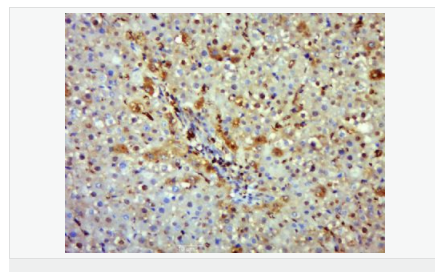

產(chǎn)品應用WB=1:500-2000 IHC-P=1:100-500 IHC-F=1:100-500 Flow-Cyt=1μg/Test ICC=1:100-500 IF=1:100-500 (石蠟切片需做抗原修復)

免 疫 原KLH conjugated synthetic peptide derived from human iNos/Nos-2:1051-1153/1153

Expressed in the liver, retina, bone cells and airway epithelial cells of the lung. Not expressed in the platelets.